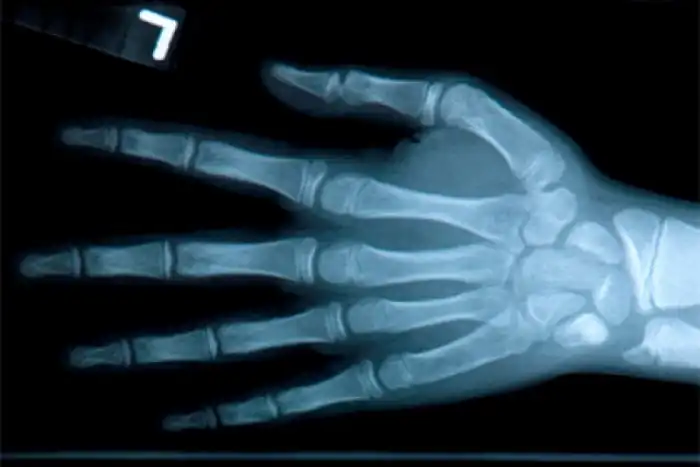

Рентгеновские лучи были открыты в 1895 году в результате экспериментов Вильгельма Рентгена. Физик работал с электронно-лучевой трубкой и несмотря на то, что она была закрыта, люминесцентный экран поблизости начал светиться. Лучи каким-то образом освещали стоящую перед ними поверхность.

Рентген пытался заблокировать лучи различными предметами, но все было безуспешно. Но когда физик положил перед трубкой руку, то увидел, что изображение его костей проецируется на экран. Используя фотографическую пластинку, Рентгену удалось зафиксировать полученную картинку.

Позже данную технологию стали использовать большинство медицинских учреждений по всему миру. Уже сейчас известно о негативном влиянии рентгеновских лучей: желательно не облучаться чаще 2 раз в год.